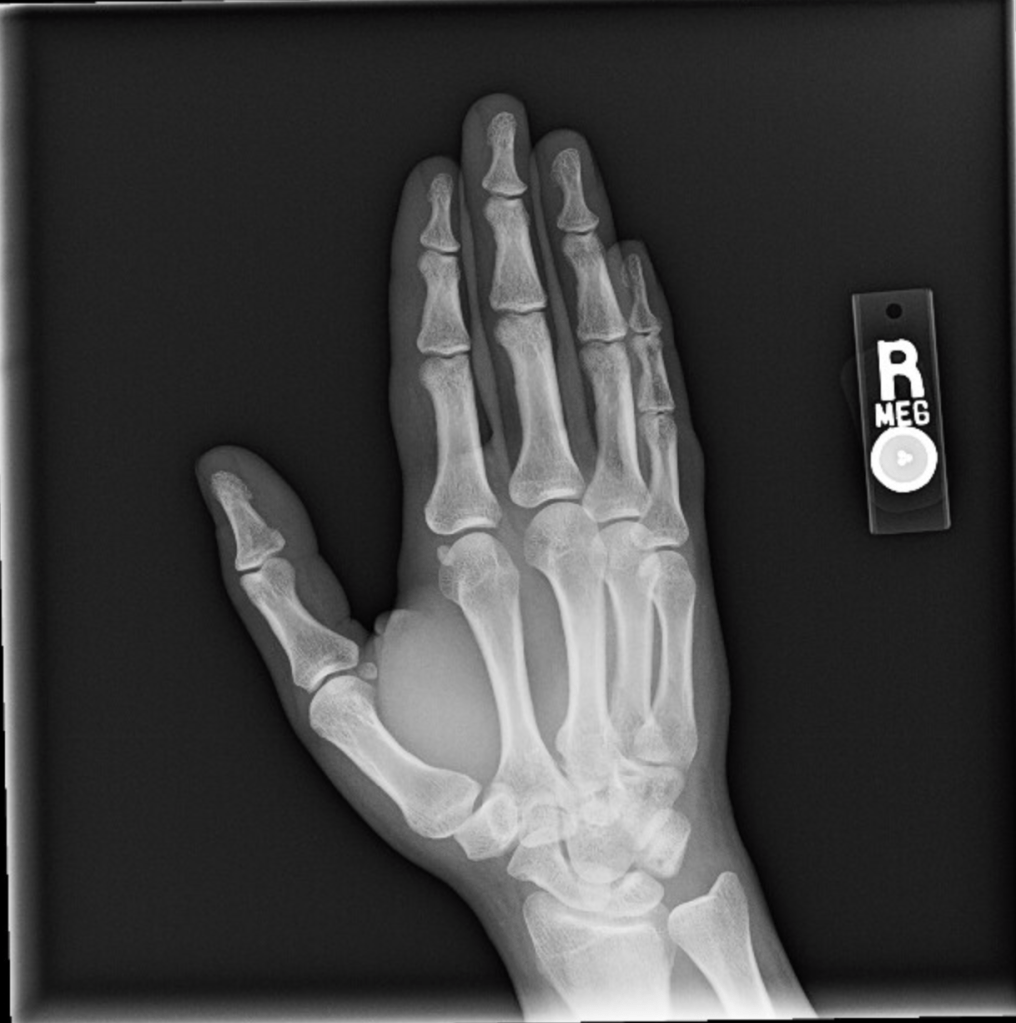

The reason I injured my wristโresulting first in probable tendonitis that made it basically impossible to use my right hand and then some mysterious secondary condition(s) that initially meant my left arm got really sore really easily and now is more of a joint thing that’s affecting both my hands and, to a lesser extent, all of my joints, but is probably not arthritis based on preliminary blood tests (my doctor thinks it’s carpal tunnel, but the test for that is booked until June)โis definitely not at all embarrassing, not at all something that I had advance warning of and could have easily avoided if I’d just listened to what my body was telling me, definitely don’t click that arrow.

I wake up in the morning with an odd discomfort in my right pinkyโwhen I unbend it, I get this weird kind of clicking feeling at the base. It's a little distressing but goes away after about an hour, so I ignore it. And sure my wrist hurts from all the tiny handwriting...and the several hours of Elden Ring and/or Need For Speed Unbound I play in between writing sessions, but I keep stretching it out and figure that's good enough. And I keep on that way through Friday as wellโafter waking up with the same weird pinky issue. Which I also have Saturday morning.

At this point I'm pretty sure something's going on, so I scale things back, but it's not until I wake up on Sunday feeling downright sore that I put a stop to all nonessential wrist functions. I call out of work, take the day to rest, go to bed early, and figure I'll feel basically fine tomorrow.

At approximately 11:30 pm I wake up and can't move the fingers on my right hand.

So April 3rd is my first appointment with the hand specialist. My assumption for how this is going to go is that I’m going to explain my symptoms and he’s going to say, “Yeah, that’s pretty standard for this kind of injury, here’s some sort of medication or some other specific treatment and a referral for physical therapy.” That is not what happened. After I explained my symptoms he had me do all these movements with my hands that the urgent care physician had had me do and had then told me that I definitely didn’t have carpal tunnel, and so of course the hand specialist tells me he thinks it’s carpal tunnel. “So the test for that is a nerve conduction study, those usually take a while to open up so we’ll try to get that process started as soon as possible, and in the meantime we can run some more blood tests just to rule out arthritis.” “How long is a while?” “Probably two months.”

- It has, at time of writing, been 13 weeks. My nerve study is in 4 days. My next doctor’s appointment to discuss the results is in a week. My hands are still hurting.